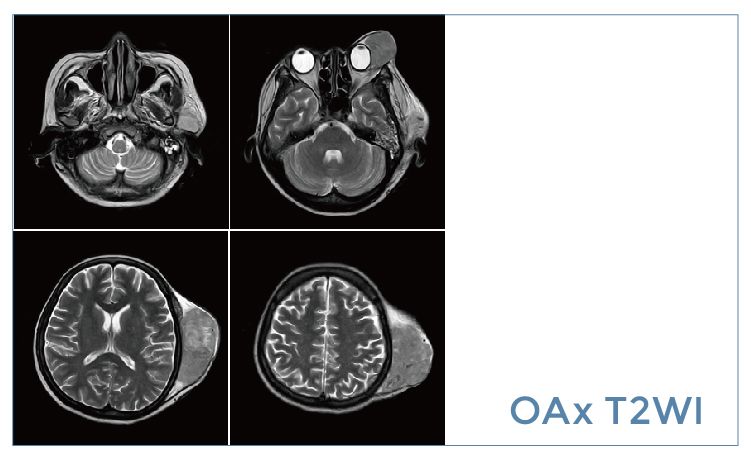

【朗润影像档案】磁共振影像病例分享(编号20190920)